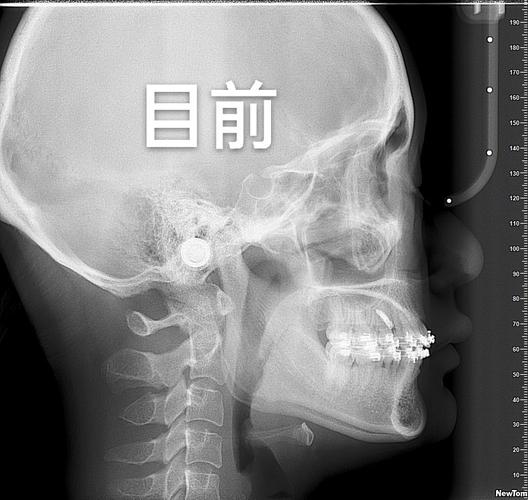

- 项目:口腔检查(视诊、探诊)、拍片(全景片、侧位片、CBCT,部分机构免费)、取模(传统或3D口扫);

案例1:成人骨性龅牙矫正(王女士,28岁,杭州)

- 问题:上颌前突,侧颜“凸嘴”,不敢大笑;

- 方案:拔除4颗前磨牙+隐适美隐形矫正;

- 效果:矫正1年8个月,牙齿排齐,龅牙改善,侧颜线条自然,自信心提升;